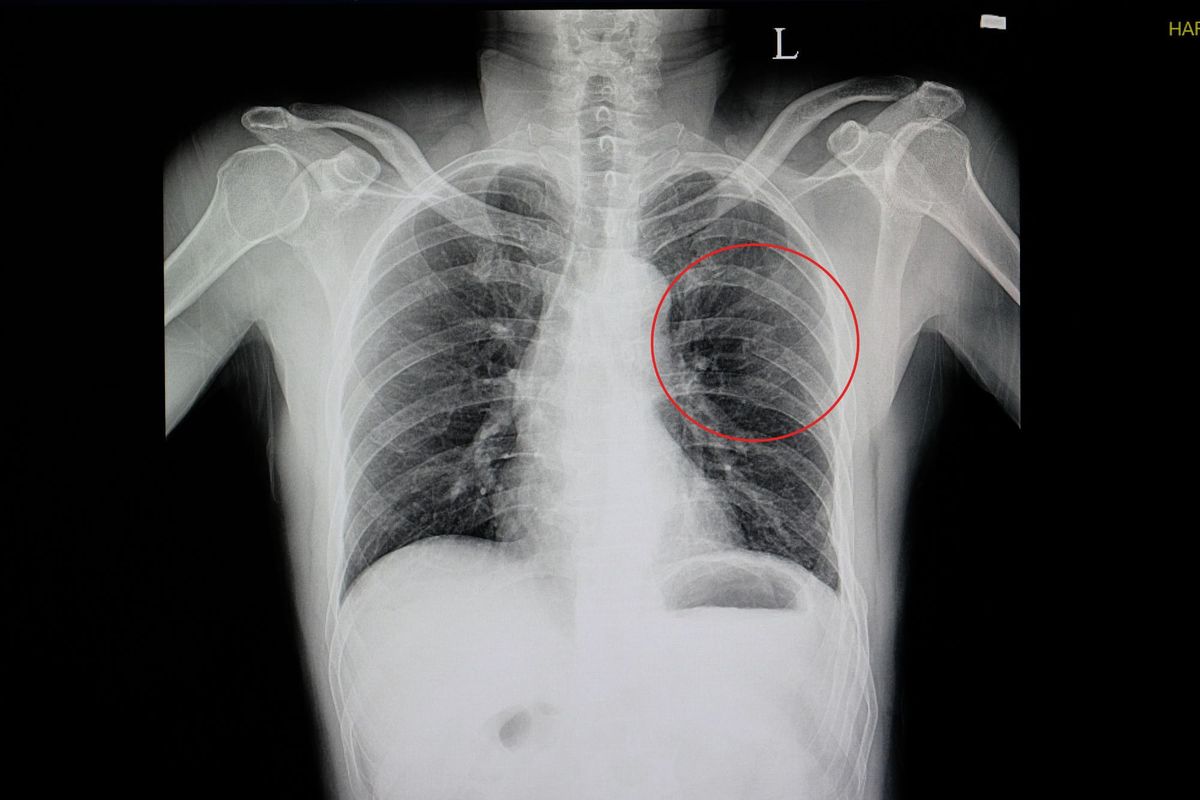

Болевые ощущения в ребрах как один из признаков невралгии могут менять свой характер: нарастать при вдыхании воздуха и при его выдохе, изменяться от положения тела или движений. Злокачественные новообразования костной ткани также сопровождаются неприятными ощущениям в области грудной клетки. Различают несколько видов остеосаркомы. Это онкологическое заболевание характеризуется быстрым прогрессированием и склонностью рано давать метастазы. Ему одинаково подвержены люди разных возрастных групп. Боль в ребрах — также типичный симптом плеврита. Этот недуг представляет собой воспалительный процесс, затрагивающий мембрану, в которой находятся легкие. Боль в области ребер в таком случае имеет тупой характер. Кроме того, это заболевание сопровождается ярко выраженным ограничением подвижности грудины.

Диагностика

Боль в ребрах — это всего лишь один из симптомов патологии. Для того чтобы избавиться от нее, нужно обратиться за помощью к врачу травматологу, неврологу или терапевту. Дальше нужно будет пройти обследование и устранить само заболевание. Вам могут назначить один или несколько из нижеприведенных методов диагностики:

Боль в рёбрах — может быть следствием межрёберной невралгии, травмы, остеохондроза или внутренних заболеваний. Промедление с обследованием усиливает риск формирования хронического болевого синдрома. Считаю важным осмотр невролога и исключение сердечных и легочных патологий. Диагностика проводится с помощью УЗИ, ЭКГ и рентгена. Также учитывается образ жизни и уровень нагрузки. Без терапии возможны выраженные болевые ощущения и ограничения подвижности.